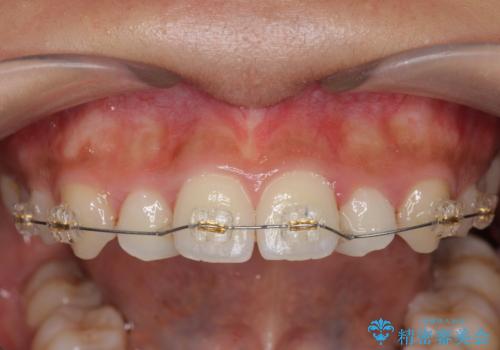

- インビザライン +部分ワイヤー矯正

- 1年2ヶ月

上顎前歯のみの部分ワイヤー治療を約6ヶ月行い、ねじれの問題を解決したのち、マウスピース矯正で細かな歯列を整えていきます。